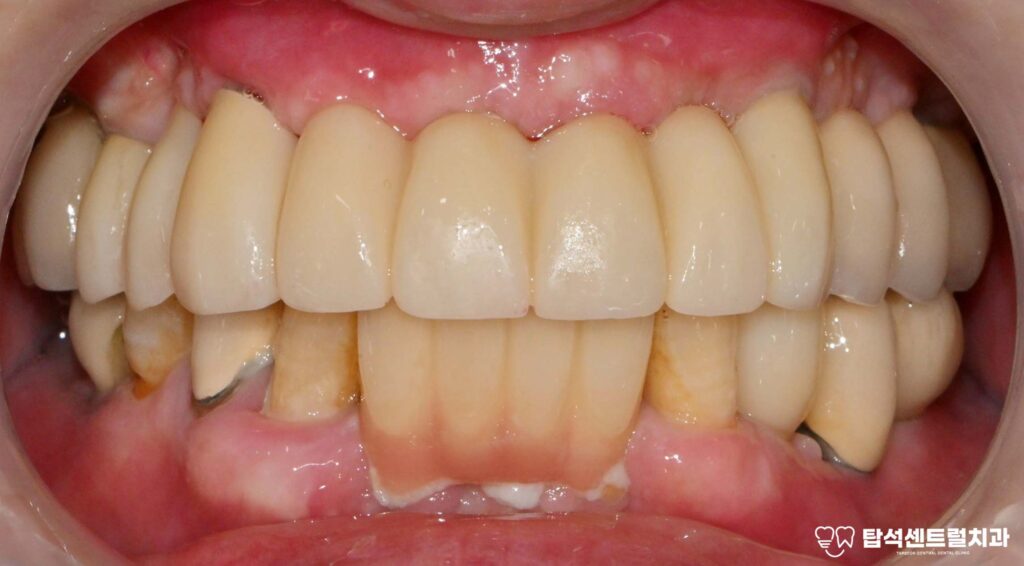

이후 잇몸이 회복되면 제작할 보철의

색을 고릅니다.

자연스러운 색으로 제작하여야,

보철을 올렸을 때도

어색한 느낌 없이 조화로워 보입니다.

최종 보철을 제작하기 전까지

임시 치아를 올려 심미성과

저작 기능을 잃지 않도록 합니다.